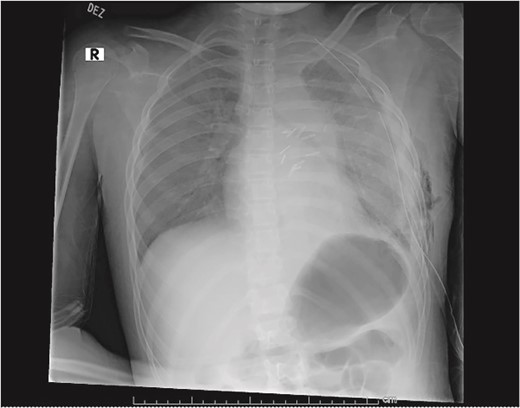

Our patient is a 10-year-old Caucasian female with a history of early adrenarche, ADHD, and COVID-19 and no past surgical history. She presented to the ED with a month-long history of persistent coughing, shortness of breath on exertion and speaking, and left-sided chest pain that began after a diagnosis of mildly symptomatic COVID-19. A physical exam revealed decreased breath sounds on the left, with a left-sided chest protrusion. A plain film and CT demonstrated a normal right lung, with a significant mediastinal shift toward the right, displacement of the heart into the right hemithorax, with complete whiteout of the left hemithorax, and demonstrating a mix of solid and cystic foci, with a round opacification at the left lung base (Figs 1 and 2). The patient underwent an uncomplicated left thoracotomy with excision of two masses, one being 22.5 × 21.0 × 10.5 cm and the other being 13.5 × 11.5 × 6.2 cm. These masses weighed 2394 g in aggregate. The specimens consisted of well-encapsulated tumors attached to the posterior aspect of the chest wall. A regional, positive lymph node measuring 3.0 × 2.2 × 1.0 cm was also resected. Due to the large size of the tumor and the requirement for clean margins, parts of the latissimus dorsi and serratus anterior muscles were also resected. By postoperative day (POD) 0, the left lung had already filled the left hemithorax, and the mediastinal shift had corrected (Fig. 3). The chest tube was removed on POD 5, and a plain film showed continued expansion of the lung to full size and resolving pulmonary edema and atelectasis (Fig. 4). The patient was discharged home on POD 5. The tumor staging was T4N1M0. The tumor was positive for vimentin, CD56, synaptophysin, chromogranin, and NSE. The tumor was negative for pancytokeratin, Cam5.2, EMA, S100, desmin, SMA, SOX10, HMB45, CD117, DOG1, CD99, PR, CD68, WT1, CD30, p53, Alk1, GFAP, and nuclear β-catenin. Next-generation sequencing showed an MGA:NUTM1 fusion, supporting a final diagnosis of high-grade MGA:NUTM1 fusion SCS. Given the size and grading of the tumor, the patient underwent adjuvant CT-RT with ifosfamide, doxorubicin, and proton beam radiotherapy, with supportive doses of MESNA and dexrazoxane for 4.5 months post-operatively. The basis of this treatment is ARST0332 Arm C [6]. Before treatment initiation, the patient underwent an uncomplicated left oophorectomy for reproductive cryopreservation. A PET/CT prior to CT-RT showed hypermetabolic activity in several areas. These included the pleural resection margin, a mediastinal lymph node concerning for metastasis versus postsurgical change, and a left axillary lymph node concerning for metastatic disease. During treatment, the patient contracted human metapneumovirus and rhino/enterovirus, resulting in febrile neutropenia. The patient was successfully treated with blood and platelet transfusions and pegfilgrastim. Upon completion of CT-RT, PET/CT imaging showed no evidence of residual disease, with minimal focal hypermetabolic activity as compared to the previous imaging (Fig. 5).

Plain film showing complete left hemithorax opacification and mediastinal shift (arrows) to right.